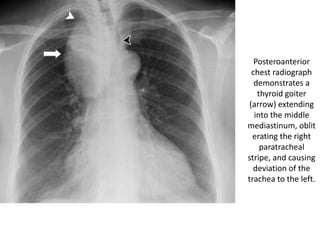

Posteroanterior

chest radiograph

demonstrates a

thyroid goiter

(arrow) extending

into the middle

mediastinum, oblit

erating the right

paratracheal

stripe, and causing

deviation of the

trachea to the left.